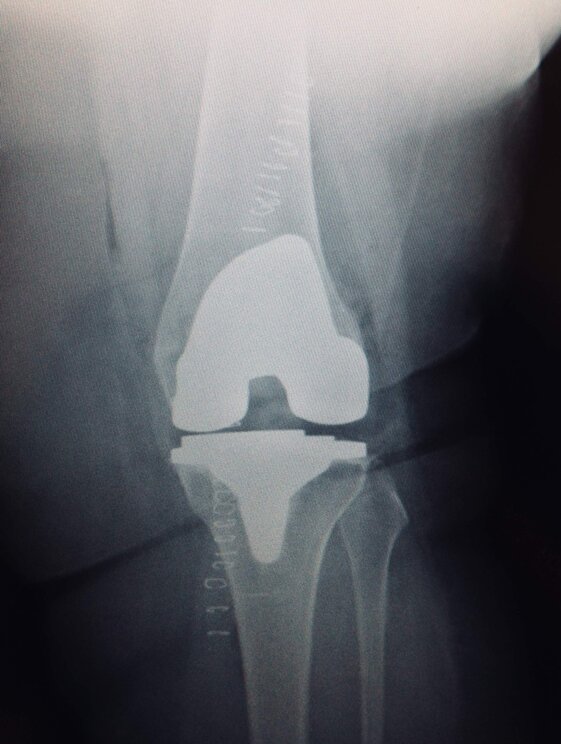

Radiografie post-operatorie in AP di interventi chirurgici di artroprotesi cementate di ginocchio eseguiti in due pz con allergia ai metalli (nichel). Sono state utilizzate due protesi di due arche differenti, entrambe anallergiche (nichel-free) con conservazione del LCP (CR)